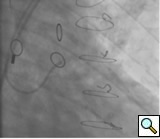

In the past, surgeons used rings to mark the ostia of the vein grafts substantially aiding the angiographer to localize the vein graft ostia during angiography. However, nowadays, it is not a usual practice. The lack of marker can increase the contrast use and radiation particularly in patients without the knowledge of the types and number of vein grafts. As mentioned earlier, right coronary grafts have usually a right sided take off from the aorta. Therefore, using standard view, left anterior oblique (LAO), which is used for right coronary artery catheterization is the view of choice. Left coronary bypass grafts have usually anterior take off. Therefore, a right anterior oblique (RAO) makes it easier to engage the left-sided vein graft ostia preventing foreshortening of the catheter tip. Using RAO, the catheter tip should be oriented to the right side of the screen. The vein grafts to the left system is based on the anatomical proximity of the native coronary to the aorta. Therefore, LAD graft ostia are usually closest grafts to the aortic valve followed by diagonal and circumflex grafts. Circumflex graft ostia usually have the highest take off from the aorta. There are occasional cases with different take off making vein graft angiography difficult. In such a situation, the angiography catheter has to be probed across the aorta in different level in order to engage the ostial vein graft. A non-selective strong contrast injection or aortogram may be necessary to delineate the unusual take off of missing vein grafts or documenting total occlusion of missing vein grafts. Total occluded vein grafts usually have a residual knob in the aorta that can be seen during angiography.

The most commonly used catheters for left heart catheterization and vein graft angiography can be seen in Figure 1 and Figure 4-13. Most of the vein grafts have horizontal take off and can be successfully engaged using a commonly used Judkins right number 4 (JR4) catheter. The JR4 catheter is the most commonly used catheter for the engagement of the right coronary ostium with horizontal take off. However, many vein grafts have unusual take off requiring different catheters. Many right coronary vein grafts have steep inferior take off making the ostial engagement with JR4 difficult or impossible (Figure 10). In such a scenario, a multipurpose catheter which has a shallow angulation is the best choice (Figure 11). The second major challenge in engaging vein graft ostia, particularly vein grafts supplying the left coronary arteries, is the shape of the aorta. A large aorta can make it very difficult for the JR4 catheter to reach the ostial vein grafts. In such a situation, Amplatz (AR) right and left (AL) catheters can be very helpful to reach the vein graft ostia. Amplatz catheters have a larger primary curve and have been used successfully in unusual superior take off of left coronary arteries or vein grafts and in large aorta. Amplatz catheters are available in different sizes (from smaller to larger curve: AR 1, AR2, AL2, AL2 and AL3). Occasionally, a very superior take off of a vein graft requires specially designed bypass graft catheters. Amplatz catheters are also extremely helpful in engaging native right coronary ostium with anterior take off.